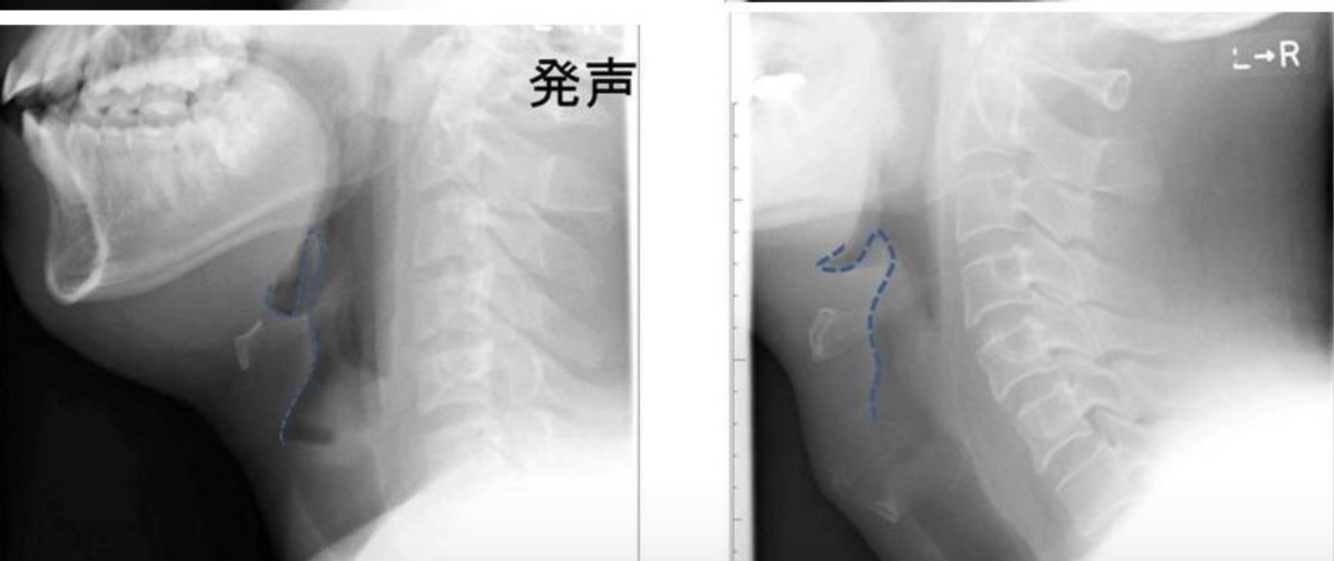

Diagnosis:

- clinical

- XR: ‘thumb sign’ and ‘steeple sign’